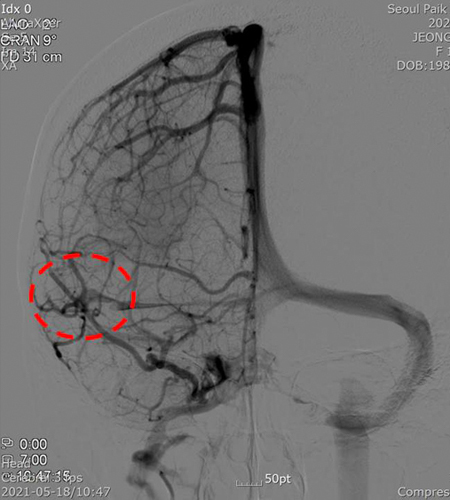

Before healing [Cerebrovascular angiography]

Ō¢▓ Arteriovenous malformation is seen.

Ō¢▓ Suspected cerebral artery malformation was observed in the MRA performed after visiting the emergency room of the hospital for the above patientŌĆÖs headache and tinnitus. On May 18, 2021, he was admitted to the neurosurgery of the hospital and was diagnosed with the above diagnosis after performing a detailed examination (Cerebrovascular angiography) on the same day. This requires continuous follow-up and treatment in the future.